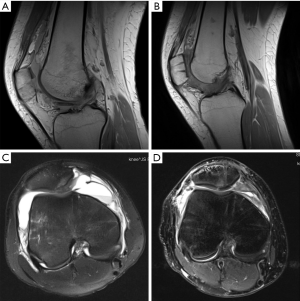

Each patient had two-viewed X-ray (Figure 2A), CT, and MR exams preoperatively. MRI showed lateral femoral condylar bone marrow edema and MPFL lesions (Figure 2B). Computer tomography reconstruction images were also available for further diagnosis of the OCFs (Figure 2C,D). All 18 patients underwent X-ray (Figure 3) and MRI examinations postoperatively. Postoperative MRI showed the fixation fracture fragments and the image of drill channels (Figure 4). All of them showed good healing of the OCFs. However, the MRI showed that 4 patients had anterior patellar bursa with no clinical symptoms. There were small areas of cartilage thinning but no obvious sign of joint degeneration.

Additionally, suture fixation may cause anterior patellar bursa by leading fluid flow through the bone tunnel (29). In this study, we also found that 4 out of 18 patients had anterior patellar bursa after surgery without obvious symptoms.